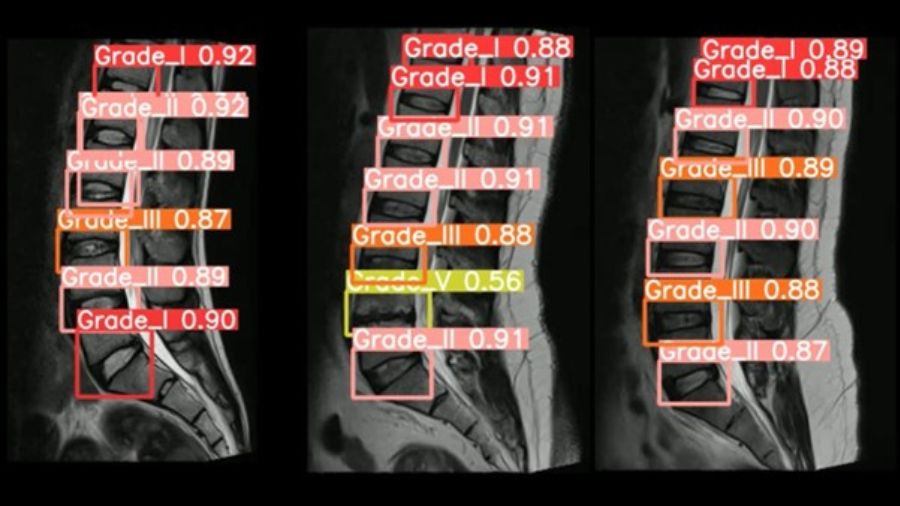

This review showcases how AI models, specifically CNNs, were used to diagnose and grade lumbar DDD. These models consistently outperformed traditional diagnostic methods, achieving accuracies as high as 99.5% in certain studies.

This exemplifies how ML can be applied in spine research to enhance diagnostic precision (Figure 4).1,3

- Supervised learning in action: Supervised learning involves training a model with labeled data. In the case of lumbar DDD, AI models were trained using MRI images labeled with the Pfirrmann grading system to classify disc degeneration.4This approach resulted in high diagnostic accuracy across multiple studies.

- Deep learning and Convolutional Neural Networks (CNNs): Deep learning techniques, such as CNNs, were employed to automatically extract features from MRI images, enabling accurate identification and classification of lumbar disc pathologies. CNNs in this context proved effective in detecting subtle changes in disc morphology that may be missed by human interpretation.

- Performance metrics: The performance of ML models in lumbar DDD diagnosis was evaluated using metrics such as accuracy, sensitivity, and specificity. For example, the CNN model used by Liawrungreung et al. achieved an accuracy of approximately 95% in detecting lumbar intervertebral disc degeneration.